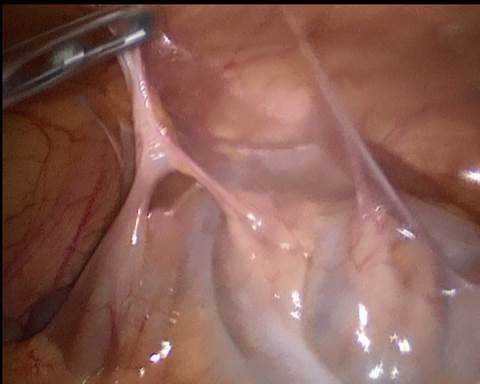

Использование РКТ исследования позволило избежать напрасного оперативного вмешательства у больных основной группы, в контрольной группе прооперированы 3 пациента (рис. 3), у остальных непроходимость купирована консервативно. В основной группе и группе контроля летальности не было.

Рис. 3. Спаечная острая кишечная непроходимость. Интраоперационный снимок